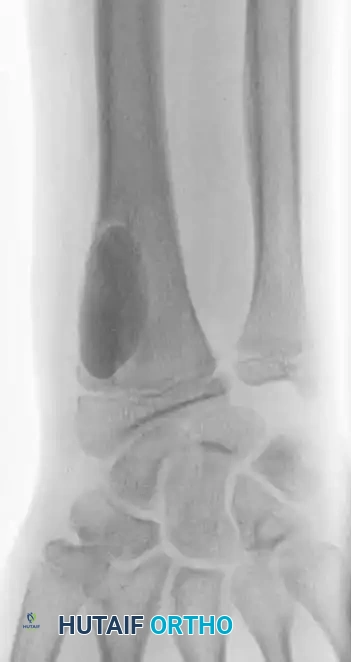

Anteroposterior and lateral radiographs of the right wrist in a 14-year-old boy showing a benign-appearing, expansile lesion in the distal radial metaphysis.